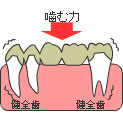

咬み合わせで歯を失うリスクが高まるというのは、例えば八重歯の方だったり、反対咬合の方などは、適切な咬み合わせの方と比べると、奥歯に側方力がかかり、奥歯を失うリスクが高まります。8020運動を達成している方はある程度、適切な咬み合わせ、歯医者の言葉で言うと、1級関係の方が多くを占めています。そのために、矯正治療をすることで、見た目を綺麗にするだけではなく、歯を守るという大きなメリットがあります。

ただ、欠損部が大きくなれば、支えている歯の負担は大きくなります。

ただ、欠損部が大きくなれば、支えている歯の負担は大きくなります。